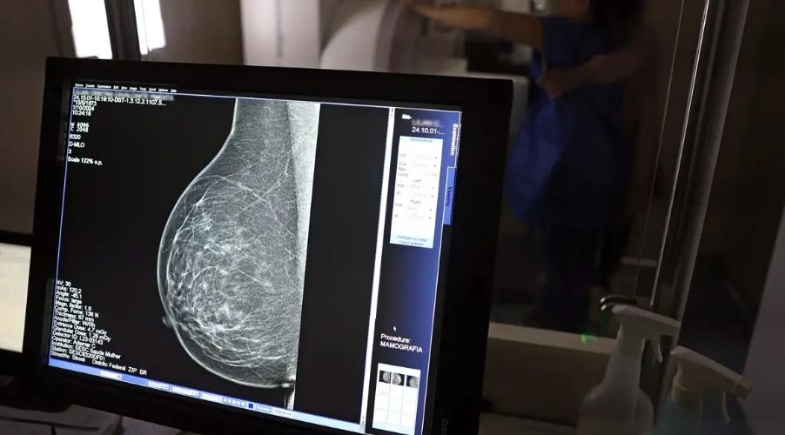

Campanha reforça importância da prevenção; uma em cada três pacientes diagnosticadas tem menos de 50 anos

Outubro Rosa: câncer de mama cresce e atinge cada vez mais mulheres jovens | Foto: José Cruz/Agência Brasil

O exame clínico das mamas e a mamografia são as principais formas de detectar precocemente a doença.